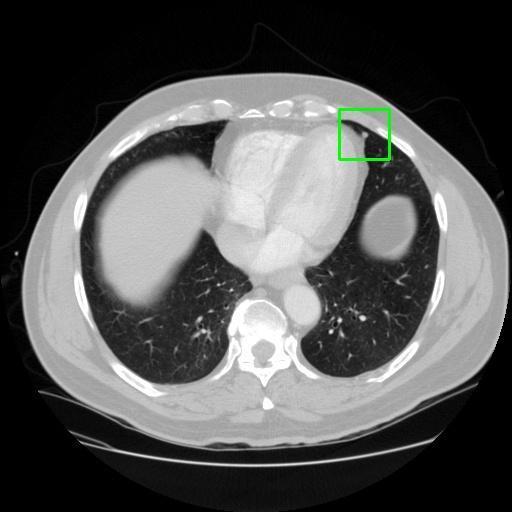

We developed an AI-based system using deep learning models for analyzing lung CT scans to detect and classify pulmonary nodules. We chose the YOLOv11 architecture for its enhanced object detection capability and adapted it specifically for medical imaging, incorporating pixel-level precision and severity classification.

Classification into three severity levels with colored bounding boxes.

Maintaining performance on small, complex features like micro-nodules tested the limits of traditional object detectors.

Designed a severity classification system that categorizes nodules into null, moderate, and severe using colored bounding boxes, assisting in rapid clinical decision-making.